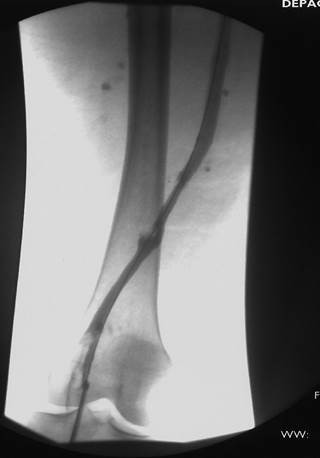

Venograma de la pierna izquierda donde se muestra un trombo oclusivo en las venas profundas más visualizadas.